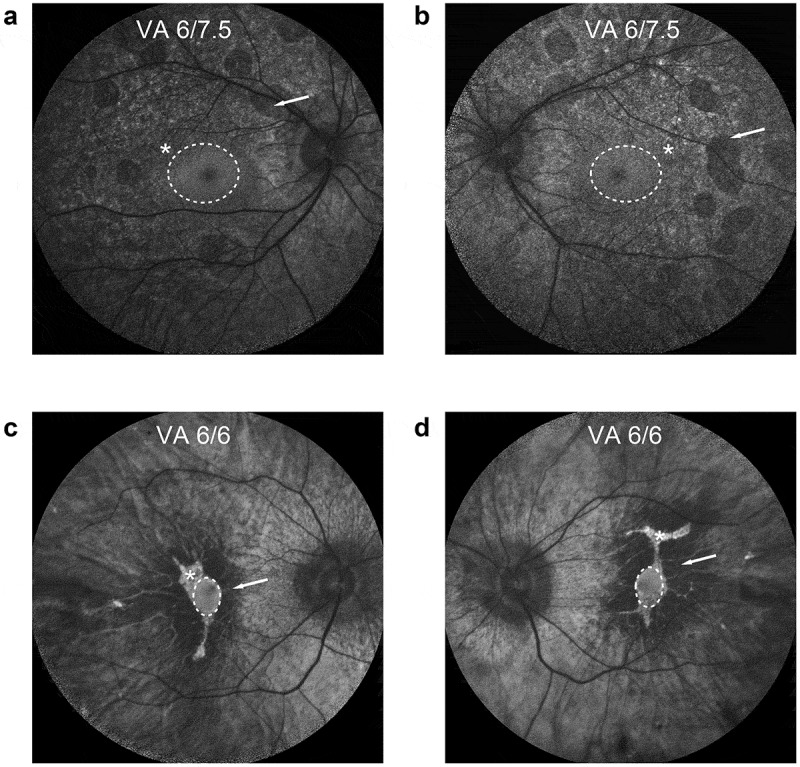

脉络膜血症是一种罕见的疾病。脉络膜血症基因治疗的基因补充方法是迄今为止最成功的基因治疗形式。当前综述的目的是概述迄今为止基因治疗试验的当前进展,重点关注此类试验的潜在和缺陷。我们提出了一个新的终点,可能对在随后的临床试验中获得监管批准具有临床意义。此外,我们还提供了进一步优化手术技术的建议。专家意见:从这项3期临床试验中吸取的经验教训,包括最佳载体设计、递送技术、患者选择标准和长期安全性,可用于开发多基因视网膜疾病的治疗方法,由于遗传复杂性,这可能需要更细致的方法。

Introduction: Choroideremia is a rare disease with a significant disease burden. Gene-supplementation methods for choroideremia gene therapy have been the most successful form of gene therapy thus far.

Areas covered: The aim of the current review is to provide an overview of current progress of gene therapy trials to date, with a focus on potential and pitfalls of such trials. We propose a novel end point that may be clinically meaningful for obtaining regulatory approval in subsequent clinical trials. Additionally, we offer recommendations for further optimization of surgical techniques.

Expert opinion: Lessons learnt from this phase 3 clinical trial, encompassing optimal vector design, delivery techniques, patient selection criteria, and long-term safety profiles can be used in the development of treatments for polygenic retinal disorders, which may necessitate a more nuanced approach due to genetic complexity.